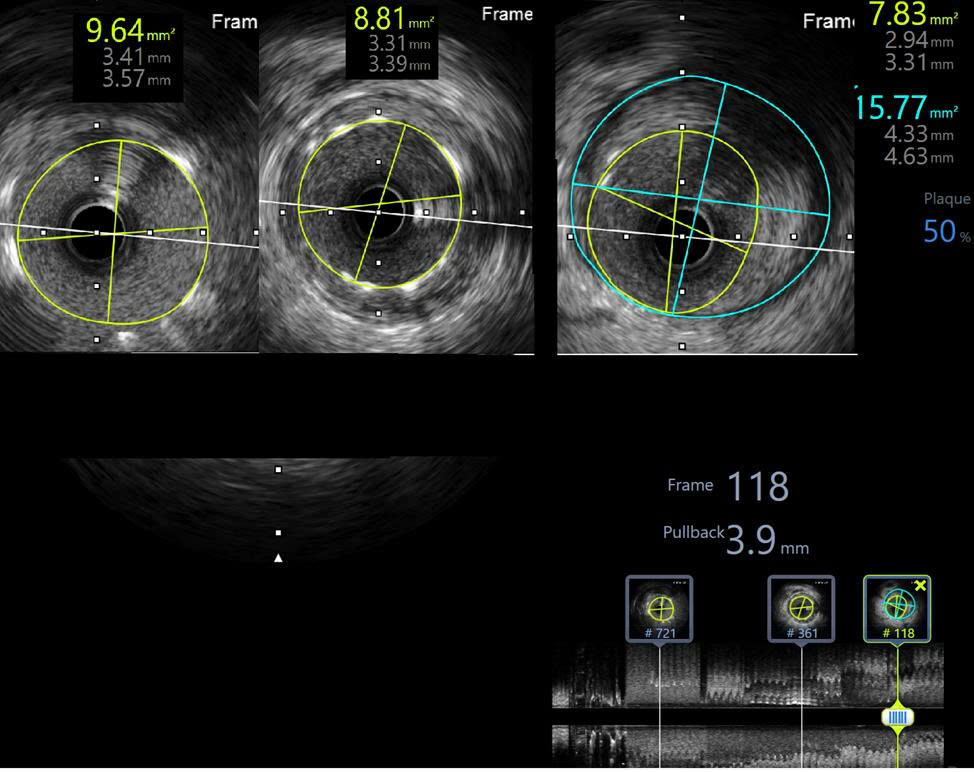

Engage the guiding catheter into the LCX ostium and advance a wire for anchoring in the LCX. After withdrawing the guiding catheter from the ostium and performing coronary angiography, it was observed that the LAD ostium originated separately from the LCX ostium and was located lower in the RAO–CRA view.Multiple attempts to selectively wire the LAD ostium using a 6 F SPB 3.0 guiding catheter (Asahi, Japan) from outside the LAD ostium were unsuccessful. The guiding catheter was then exchanged for a 6 F JL 3.5, and a Sion Blue wire was successfully advanced through the LAD ostium into the distal segment.DSA and IVUS post-intervention showed minimal stent area of 8.83 mm2, reached 112 % of distal reference vessel diameter. Stent covered LAD ostium with an area of 9.64 mm2 and was 2 mm inside the aortic artery. There was no protrusion, no dissection.